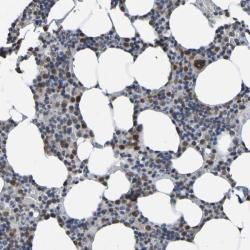

- Experimental details

- Immunohistochemical staining of human bone marrow shows nuclear positivity in bone marrow poietic cells.

- Validation comment

- Staining pattern consistent with experimental and/or bioinformatic data.